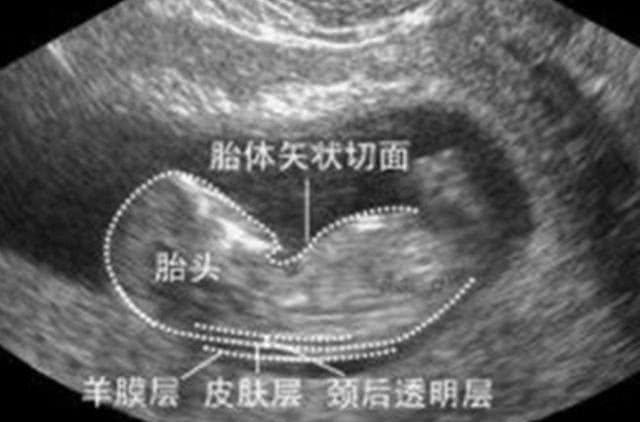

是nuchaltranslucency的简称,是指颈后透明层,即胎儿颈椎水平面皮肤到皮下软组织间的厚度。

它是目前一种通过B超手段来测量胎儿颈部皮下无回声透明层最厚部位的厚度,以此来评估胎宝宝是否患有唐氏综合征。

由于nt检查是要测量胎儿颈后透明层的厚度,因此需要在他面对B超探头的时候,且是躺着的,这样才可以清楚地看到颈部透明层并进行测量。